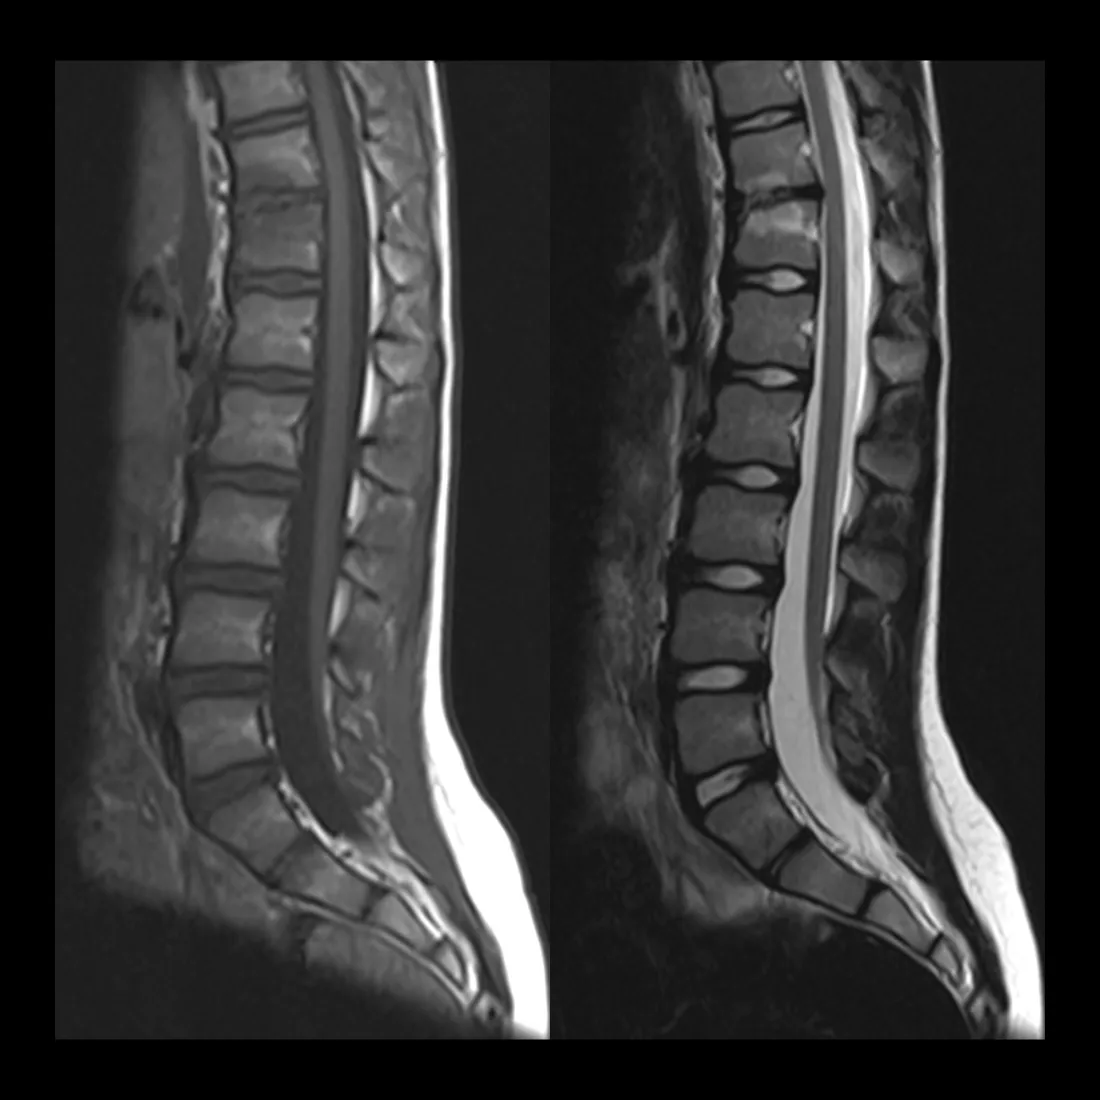

What was the tethered cord MRI about?

Before surgery, Dr. Lee wanted an MRI of my lower spine to check for a tethered cord, the idea being that if I had one, they could potentially do both surgeries at the same time. But VA insurance made it nearly impossible to turn that around before my surgery date.

So during my stay, they came back to me and said: since you're already here and everything is under the same VA referral, we'd like to get that MRI now. They were seeing symptoms that could be coming from a tethered cord, and if that was the case, they wanted to operate. The MRI came back clear. No tethered cord.

The spinal cord isn't fixed in place. It's designed to move. When you bend, sit, or stretch, the cord shifts slightly within the spinal canal. That mobility is by design.

A tethered cord is what happens when something anchors it. Scar tissue, a fatty filum, a structural abnormality. Whatever the cause, the cord gets held in place when it shouldn't be. Tension builds along nervous tissue that has no tolerance for it.

The symptoms accumulate slowly. Leg weakness, bladder dysfunction, back pain nobody can explain. Patients often spend years being evaluated for everything except the actual problem. Treatment is surgical: they find what's holding the cord, release it, and give the nervous system room to recover.